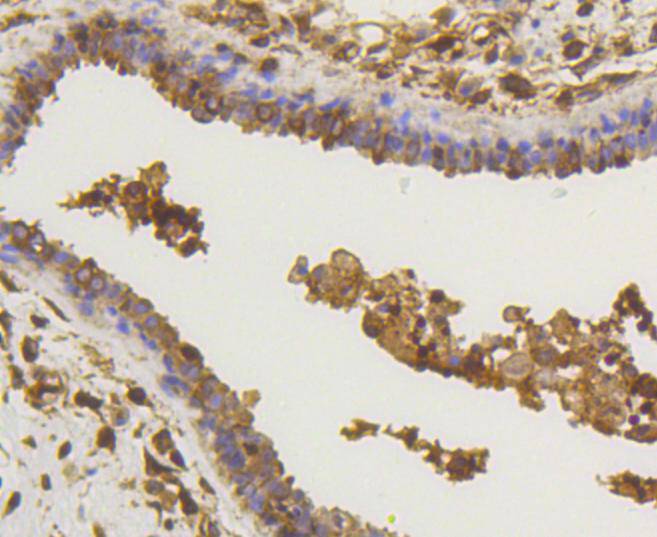

Immunohistochemical analysis of paraffin-embedded mouse lung tissue using anti-NF-kB p65 antibody. Counter stained with hematoxylin.